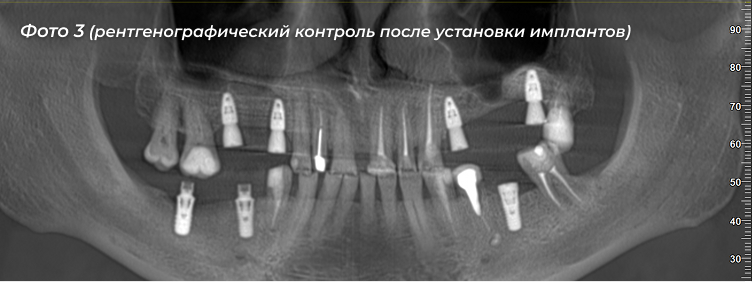

Лечение:  Был разработан поэтапный план восстановления функции и эстетики. На первом этапе  пациенту были  установлены импланты на верхней и нижней челюстях справа. На втором этапе  была проведена исплантация с левой стороны (Фото 3).